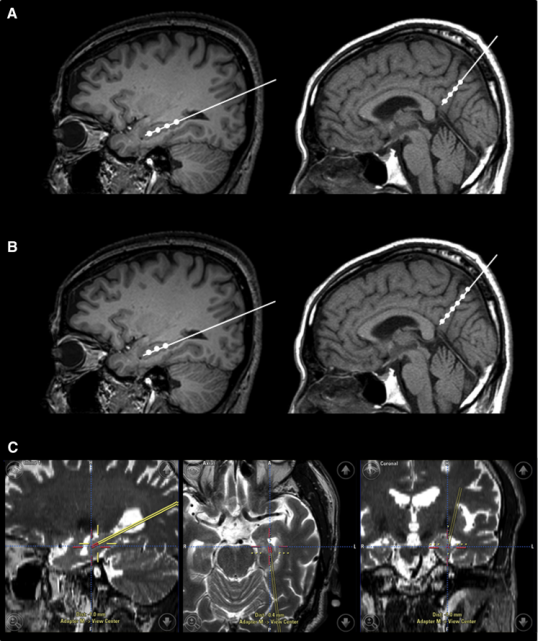

2015年,韓國首爾三星醫療中心招募了9名輕度至中度癡呆的阿爾茨海默氏病患者。Kim對9名患者進(jìn)行了一項立體定向注射間充質(zhì)干細胞的I期臨床試驗。

三名患者接受低劑量(1.0×107細胞/2 mL),6名患者接受高劑量(3.0×107hUCB-MSC 的細胞/2 mL) 。9名患者進(jìn)行了三次干細胞注射(每隔4周一次)。

干細胞立體定向注射患者的右海馬體和右前丘盤(pán)

在之后長(cháng)達36個(gè)月的跟蹤研究期間, 沒(méi)有患者出現嚴重的不良事件。由此可見(jiàn), 干細胞治療阿爾茲海默癥是可行、安全且耐受性良好的。